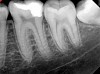

Figure 11. Preoperative radiograph. Courtesy of Dr. Guillaume Jouanny.

Figure 11

Case 2: Pulpotomy

In this case, the tooth tested vital but showed clinical signs of irreversible pulpitis. Treatment with a full pulpotomy was chosen to improve the chances the remaining pulp would survive and remain healthy. The preoperative radiograph in Figure 11 shows extensive caries in the tooth and a slightly widened apical periodontal ligament. A full pulpotomy was performed using the BC putty (Figure 12). After the putty set, a coronal restoration was placed, and an immediate postoperative radiograph was taken and viewed. At the 1-year follow-up, the tooth was asymptomatic, and the radiograph showed continued root development (Figure 13), a healthy apical periodontium, and, importantly, no calcifications in the remaining pulp (as is often seen with a calcium hydroxide therapy). A radiograph taken of the contra-lateral tooth showed similar root development (Figure 14).